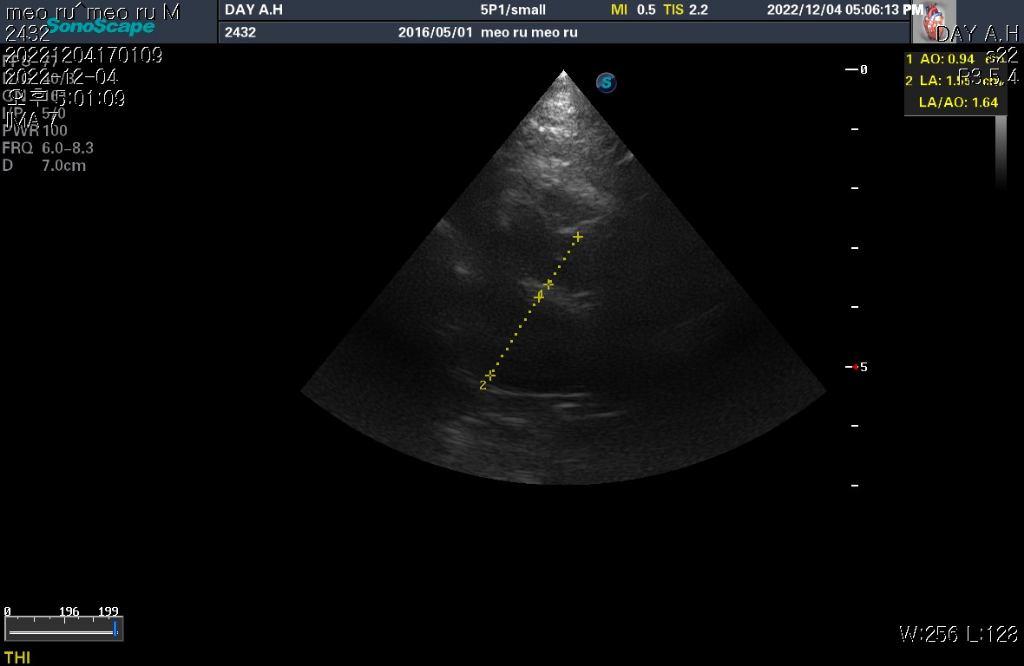

하지만 심장 질환의 잠정적 확진 golden standard는 심장 초음파 검사로 심장 초음파 검사상 심장의 벽 구조가 6mm이상이라면 HCM의 가능성이 매우 높다고 판단합니다.

현재 첨부한 사진상에서 6mm이상의 직경을 보이는 사진들이 존재하기 때문에 해당 검사를 진행한 수의사의 기준상 HCM의 가능성이 높다고 판단하는것은 합리적입니다.